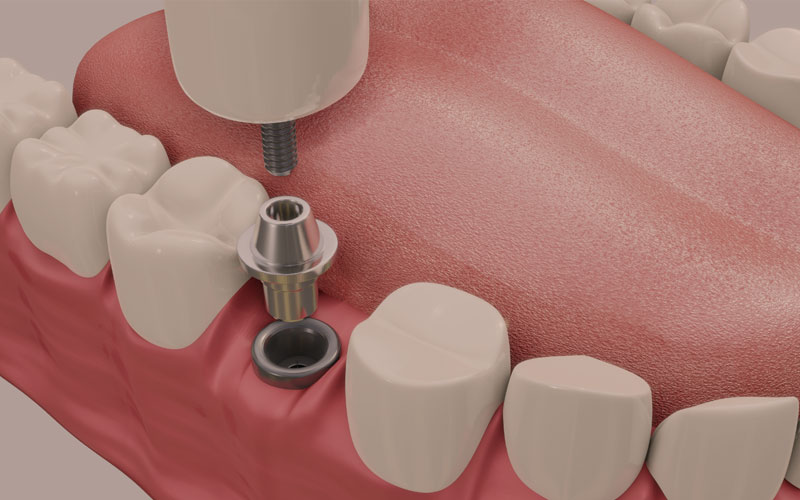

インプラント治療で取り戻した歯は、ほとんど天然歯と同じように見えますが構造に違いがあります。インプラントは、歯の根の代わりになる「インプラント本体」、歯の代わりになる「被せ物」、そしてその両方を繋ぐ「接合部」が合わさって人工の歯を作り直します。

インプラントという人工の歯の根を、歯を失った箇所のあごの骨に埋め込み、骨と結合させます。

埋め込んだインプラントを土台として、人工の歯を設置し、歯の見た目と機能を回復します。